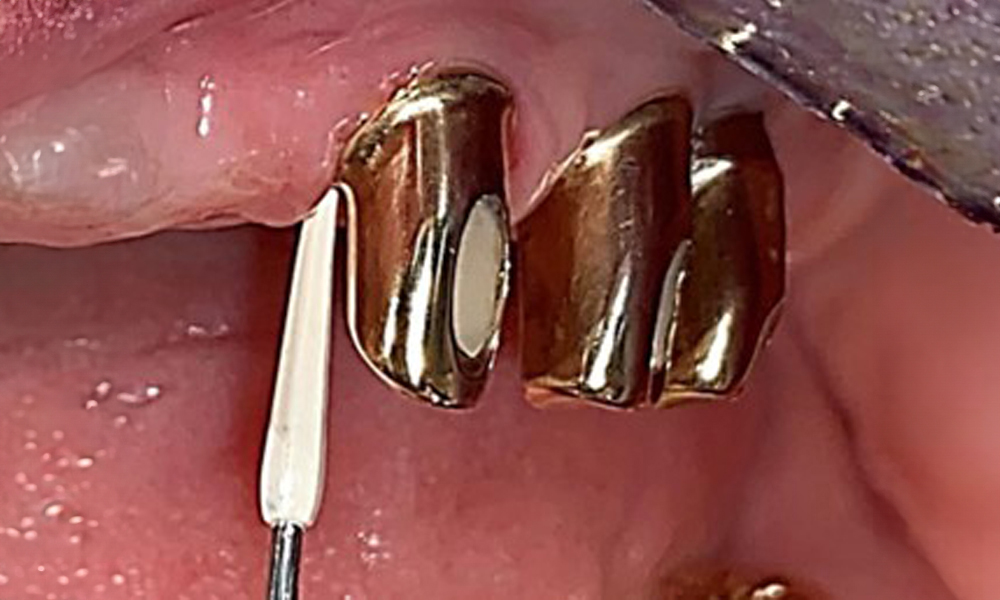

Occlusal view: Maxilla with removable, palateless denture.

Fig. 3: Occlusal view: Maxilla with removable, palateless denture.